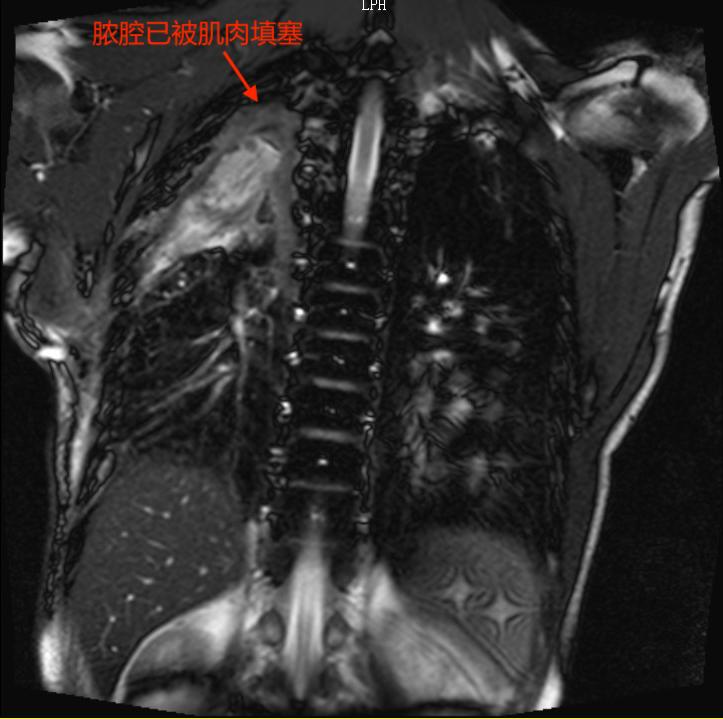

最终,专家们决定进行多学科联合手术。由呼吸科先进行支气管镜下瘘口封堵;然后,胸外科胸腔镜下清创;最后,由沈立锋副主任医师进行肌肉瓣覆盖瘘口、完全填塞胸腔彻底消灭脓腔。

经过一次胸腔镜脓胸清创引流术后,杜先生的胸部感染得到控制,引流管的引流液逐渐由脓性变得澄清起来。

手术按部就班地进行着,顺利地进行支气管瘘口封堵,然后是胸腔镜清创,就差沈医师的肌肉瓣手术了。

起初,沈医师决定用体积大、血运又非常丰富的背阔肌来填塞胸腔。

然而,手术总是存在各种变化。沈医师发现,多年的肺部疾病使杜先生丧失了大部分劳动能力,肌肉严重萎缩,单独用这块肌肉填塞胸腔,远远不够。

医生的智慧显得尤为关键,经验丰富的他当机立断,马上调整手术方案,选择增加背阔肌和胸大肌两组肌瓣联合填塞关闭胸腔。

NO.5 脓腔填塞

运用肌瓣、大网膜等自体组织对脓腔进行填塞,可彻底治愈脓胸。临床上最常用的为背阔肌、胸大肌、腹直肌瓣或肌皮瓣。肌皮瓣不仅有足够的体积和面积填补胸腔、修补皮肤溃疡,并且其丰富的血供可以有效地进行局部抗炎。带有丰富血运的肌肉组织覆盖内置封堵器并与周围组织愈合,亦可以辅助关闭瘘口,防止再发。所以肌皮瓣是消灭脓腔的最佳选择。肌皮瓣的选择要根据脓腔的大小、形状以及位置而定,常可多块联合应用治疗。